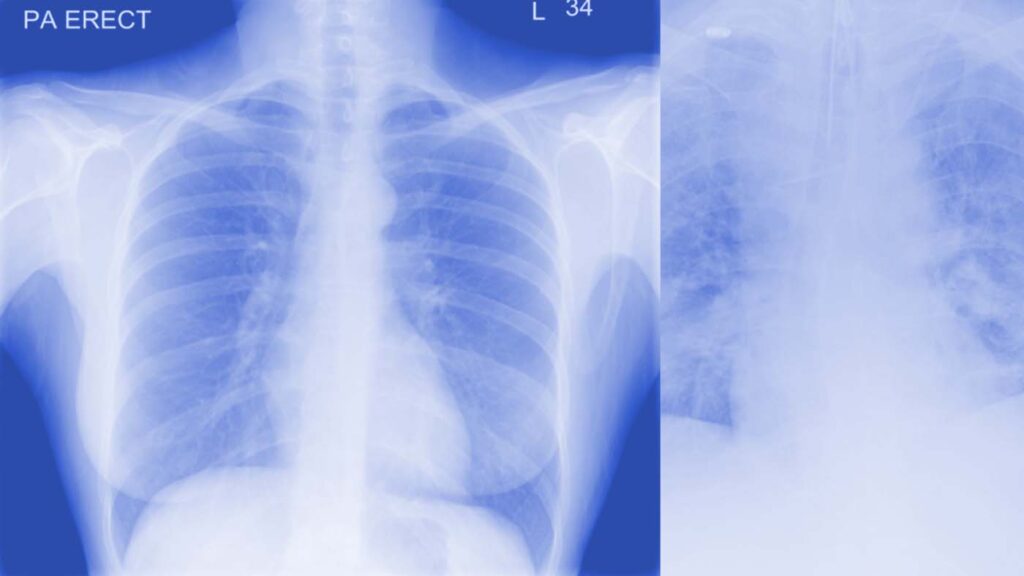

Supporting clinicians to assess COVID-19 severity using AI and Chest X-rays

COVID-19 X-rays have been a recommended procedure for patient triaging and resource management in intensive care units (ICUs) throughout the COVID-19 pandemic. Microsoft Research team worked closely with our clinicians at University Hospitals Birmingham NHS Foundation Trust to model radiological features with a human-interpretable class hierarchy that aligns with the radiological decision process. The model outperformed the clinicians across all hierarchical and multi-class tasks. To better understand the model’s failure patterns, the team employed an error analysis tool in Azure Machine Learning that is not often found in healthcare-related ML studies and is crucial for providing transparency and actionable insights about a model’s behavior. The analysis may also be useful after deployment if presented as reliability information alongside the model’s predictions.

Removing biases from deep learning-based models of COVID-19 chest X-rays

Recent research has proposed creating deep learning-based models that use chest radiographs (CXRs) in a variety of clinical tasks to help manage the COVID-19 crisis. However, due to the small size of existing COVID-19 CXR datasets, data is often pooled from multiple sources under different scenarios. Models trained on such datasets can “overfit” to erroneous features instead of learning pulmonary characteristics. This research adds feature disentanglement to the training process, resulting in better generalization performance on unseen data and outperforming other proposed methods.